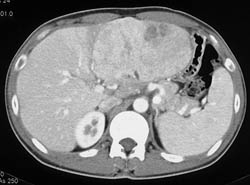

Hepatoma